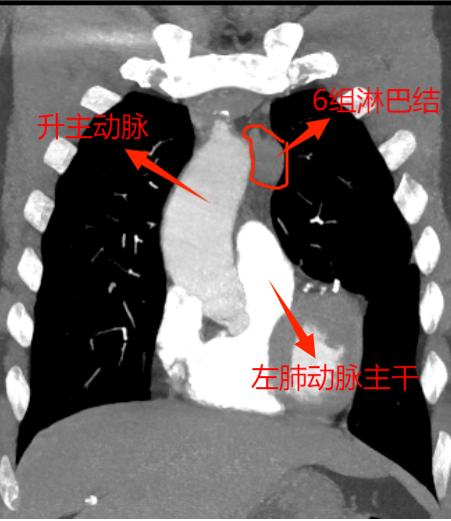

這下讓外科手術(shù)團隊為難了,因為兩組淋巴結(jié)臨近主動脈及左肺動脈2處大血管,位置深,即使CT引導下穿刺活檢,僅毫厘之差,仍大概率會出現(xiàn)大出血、氣胸,甚至危及生命,需緊急開胸,不活檢。由于轉(zhuǎn)移瘤性質(zhì)難定,影響后續(xù)方案的制定,家屬也很焦慮。

為實現(xiàn)更微創(chuàng),手術(shù)采取了單孔胸腔鏡技術(shù)。此次手術(shù),慶幸的是左肺與胸腔粘連不嚴重,但5、6組轉(zhuǎn)移淋巴結(jié)又硬又緊,與周圍組織界限欠清,尤其是5組淋巴結(jié),深埋進主動脈弓與左肺動脈根部,左主支氣管間,旁邊還有重要的迷走神經(jīng)及喉返神經(jīng)。血管損傷可能導致大量出血,神經(jīng)損傷可能造成聲音嘶啞、飲水嗆咳等并發(fā)癥。